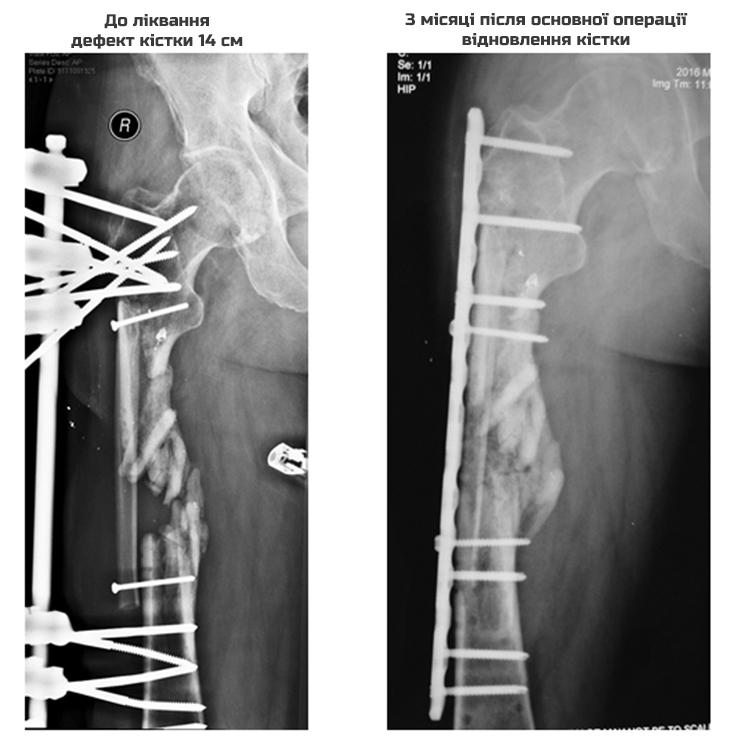

Ще один поранений боєць АТО зумів відновити свої здоров'я завдяки благодійній програмі "Біотех-реабілітація поранених". Добровольцю батальйону "Донбас" Олегу українські лікарі відростили 14 см розтрощеної важким пораненням стегнової кістки. Фінансування низки операцій забезпечили волонтери People’s Project за допомоги пожертв українців.

Чоловіка лікували у кількох військових шпиталях і за кордоном. Однак позитивного результату це не давало, тому боєць вже майже втратив надію на одужання. Подальший розвиток ускладнень травми міг призвести до інвалідності або взагалі до ампутації.

Однак завдяки новітній системі реабілітації Олег вже намагається ходити навіть без милиць.